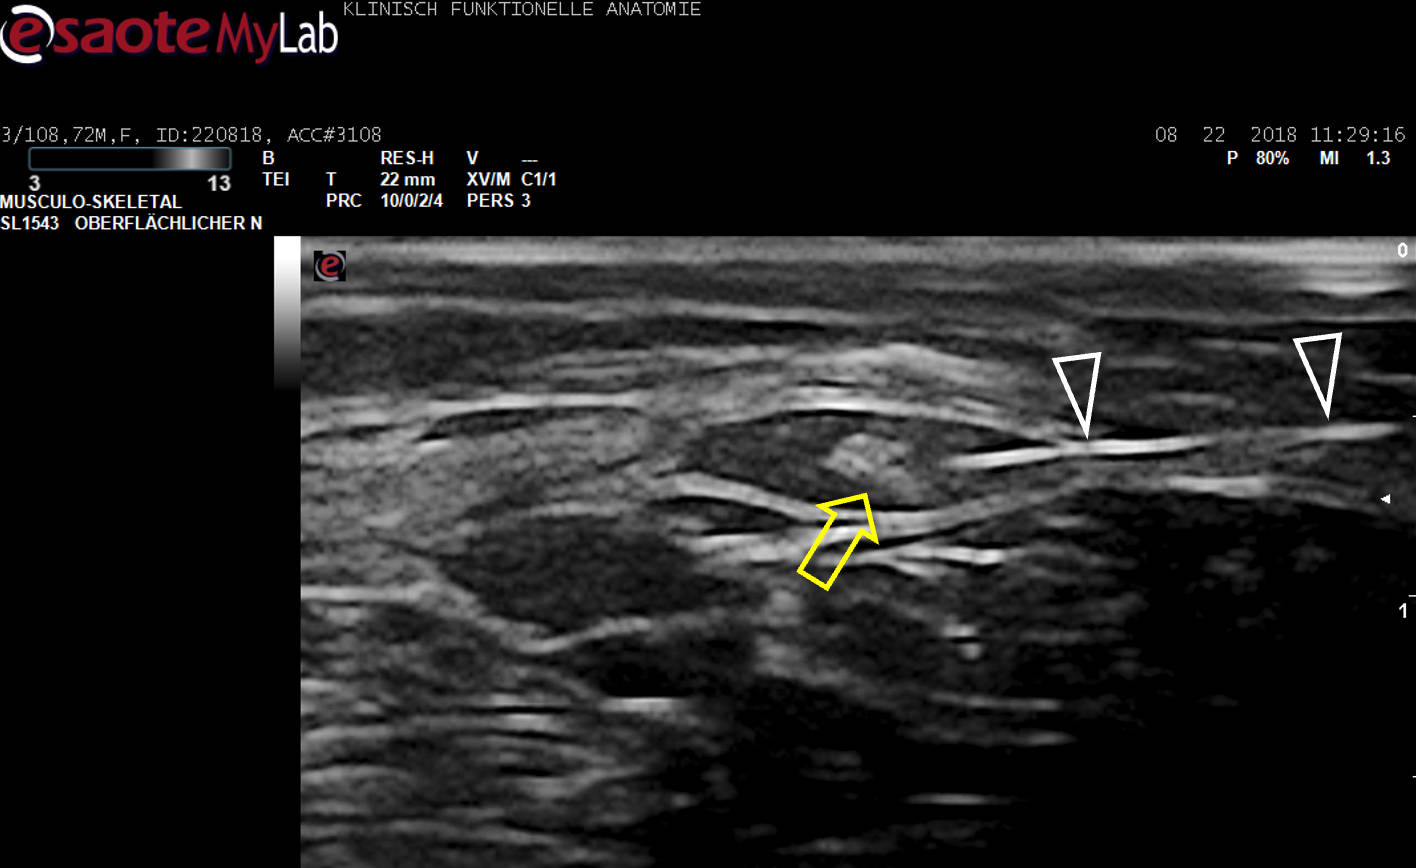

Aus unserer Grundlagenarbeit zur Anwendung des Ultraschalls (US) in der Schmerztherapie: Optimierte Darstellung zur sicheren Blockade des N. occipitalis major bei Occipitalis-Neuralgie. Heute wird der Nerv im klinischen Alltag weltweit nur noch an dieser Stelle US-gezielt blockiert!

Beispiel detaillierte Sono-Anatomie und Topographie am Lebenden.